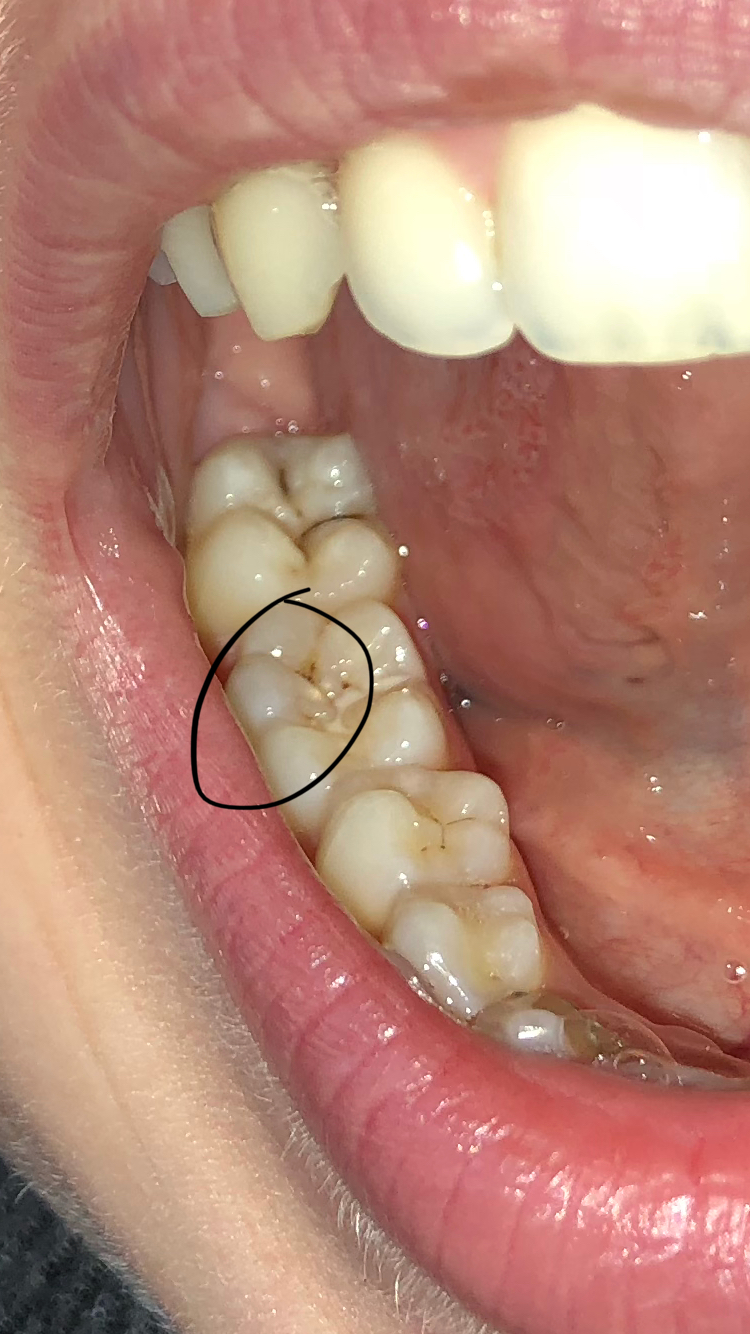

Hoe ziet een gaatje en hoe herken je ze? - Tandarts Jordaan

Hoe ziet een gaatje eruit? Zo herken je in de tanden en kiezen!

Erachter of gaatjes hebt - wikiHow